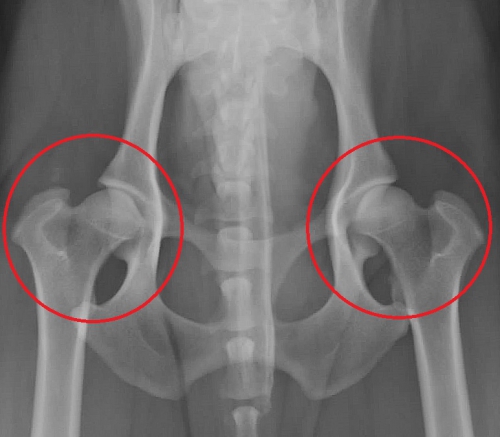

下は股関節の進行した変形性関節症のレントゲン写真です。赤丸の中が股関節ですが、大腿骨頭は変形して、関節内には骨棘の形成がみられます。同じ部位の正常写真が右です。

このワンちゃんは日常的に下肢の痛みを訴えており、運動状態によって、また寒い時期に悪化がみられます。後ろ足には常に痛みがあり、充分に動かすことができません。